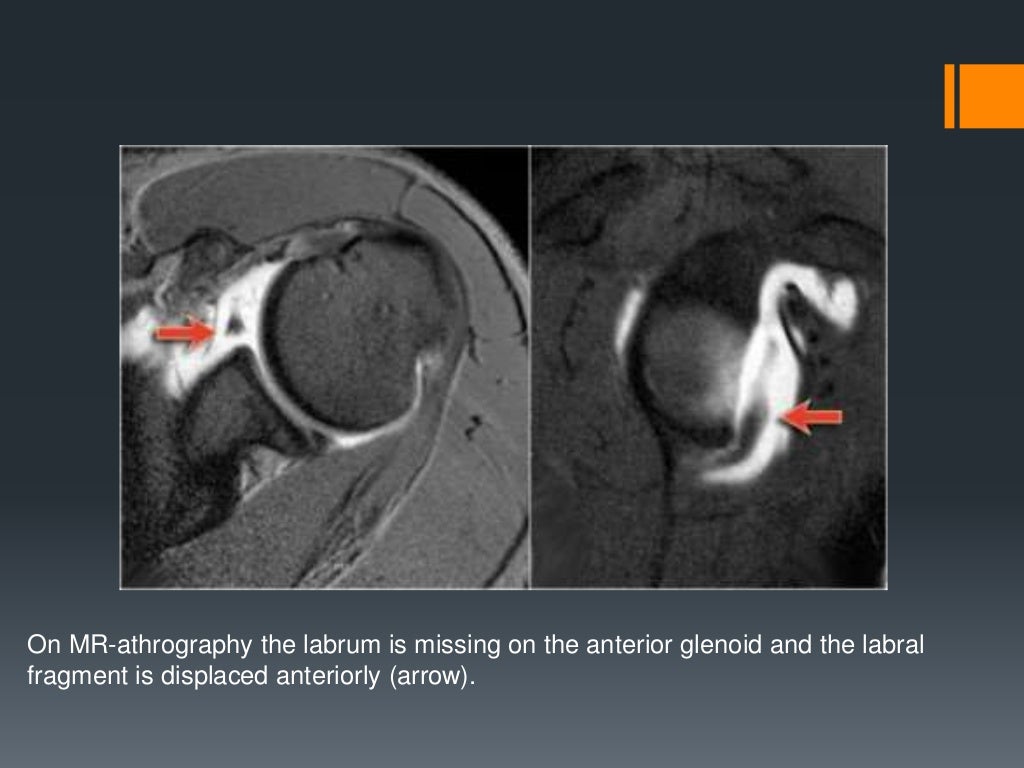

Shoulder labral tears MRI Bucket Handle Tear Shoulder Labrum Mri Web type iii slap lesion. Web the glenoid labrum, an important static stabilizer of the shoulder joint, has several normal labral variants that can be difficult to discriminate from labral tears and is subject to specific pathologic lesions (anteroinferior, posteroinferior, and superior labral anteroposterior lesions) with characteristic imaging features. Web mr arthrography of the shoulder is the most accurate established. Bucket Handle Tear Shoulder Labrum Mri.